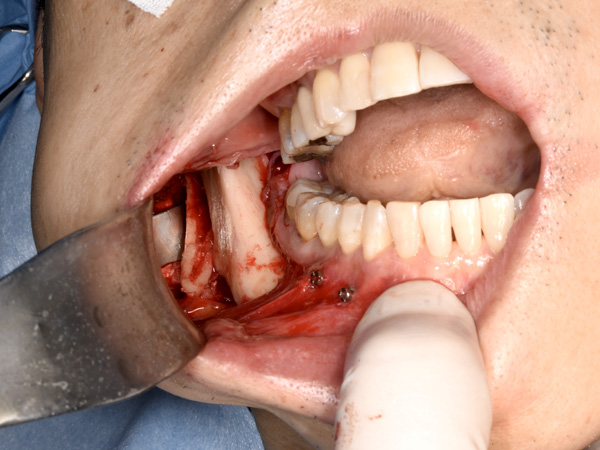

骨が切れて、分離しました。

干渉部分を鏡で確認して切除します。

ぶつかっていた骨を取り除きます。